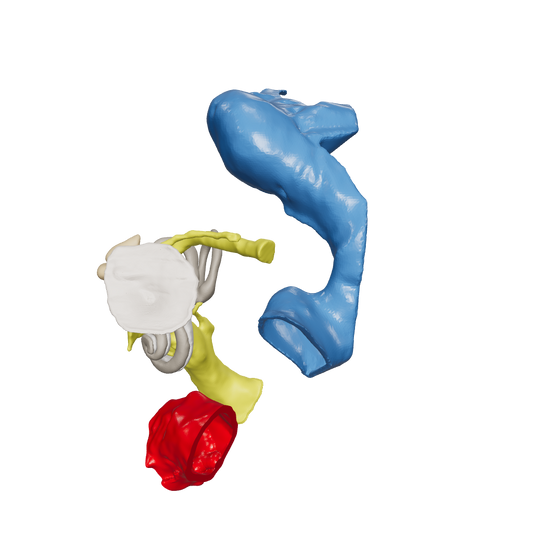

Dissect each one to learn human temporal bone anatomy, hearing and vestibular systems.

*High Contrast Colors* 3D Temporal Bones to Introduce Anatomy (6-pack)

Regular price $402.00 USDRegular priceUnit price per -